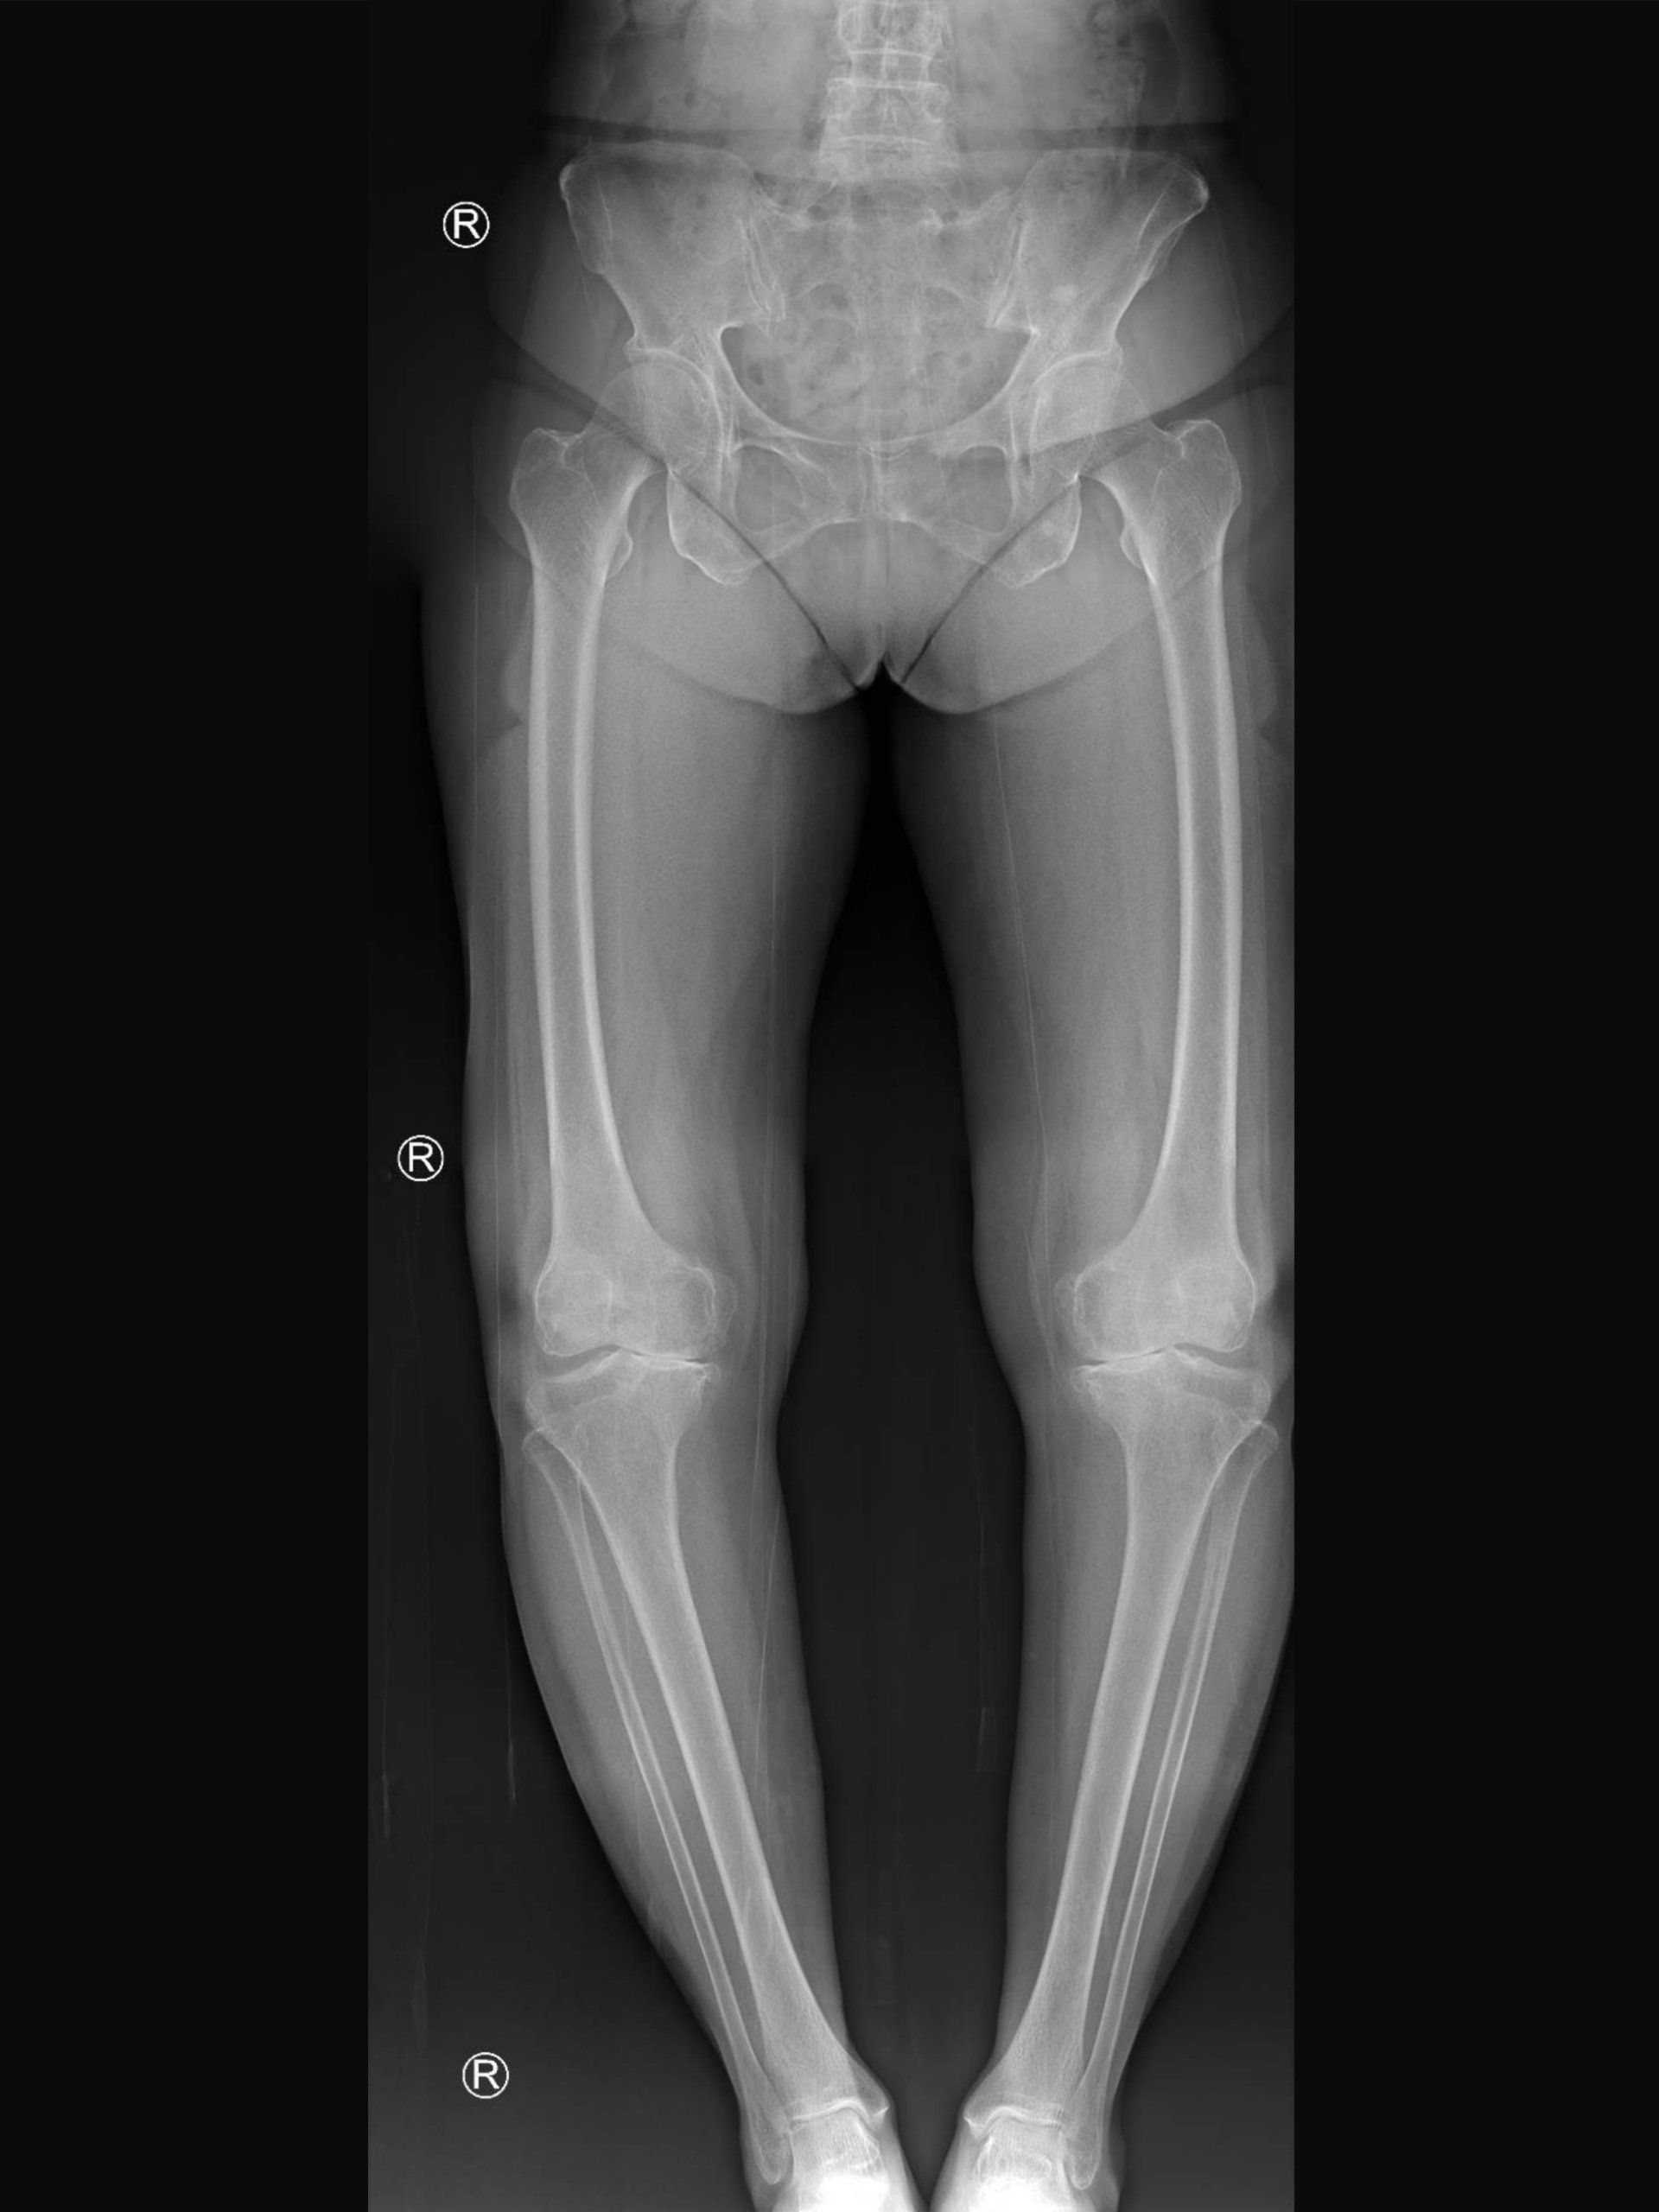

- Η γραμμή που φέρεται από το κέντρο του ισχίου στο κέντρο της ποδοκνημικής πρέπει να διασχίζει το μέσο του γόνατος:

- Αυτό ονομάζεται μηχανικός άξονας του κάτω άκρου και δείχνει που ασκούνται οι δυνάμεις στο γόνατο κατά την όρθια στάση

- Σε ένα τέτοιο σενάριο οι δυνάμεις κατανέμονται εξίσου στο γόνατο

- Όταν ο μηχανικός άξονας περνά στην εσωτερική πλευρά πάρα στο κέντρο του γόνατος, η ποδοκνημική βρίσκεται πιο κοντά και το γόνατο πιο μακριά στη μέση γραμμή του σώματος (κάθετη γραμμή ενώνοντας την μύτη και τον ομφαλό):

- Αυτό ονομάζεται παραμόρφωση του γόνατος σε ραιβότητα (ραιβογονία - ραιβό γόνατο)

- Ως αποτέλεσμα, περισσότερες δυνάμεις περνούν από την εσωτερική πλευρά του γόνατος, οδηγώντας σε πρώιμη ρήξη του μηνίσκου και του αρθρικού χόνδρου που οδηγεί σε οστεοαρθρίτιδα σε αυτή την πλευρά του γόνατος

Τι είναι η βλαισογονία;

- Όταν ο μηχανικός άξονας περνά στην εξωτερική πλευρά πάρα στο κέντρο του γόνατος, η ποδοκνημική βρίσκεται πιο μακριά και το γόνατο πιο κοντά στη μέση γραμμή του σώματος (κάθετη γραμμή ενώνοντας την μύτη και τον ομφαλό):

- Αυτό ονομάζεται παραμόρφωση του γόνατος σε βλαισότητα (βλαισογονία - βλαισό γόνατο)

- Η κακή ευθυγράμμιση των κάτω άκρων μπορεί να επηρεάσει τη μία πλευρά ή και τις δύο

- Μπορεί να επηρεάσει τη μία πλευρά περισσότερο από την άλλη

- Σε σπάνιες περιπτώσεις, το ένα γόνατο έχει παραμόρφωση σε ραιβότητα και το άλλο γόνατο παραμόρφωση σε βλαισότητα:

- Αυτό ονομάζεται “windswept deformity” καθώς και τα δυο γόνατα δείχνουν προς τη μία πλευρά του σώματος